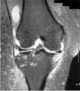

Arthritis with joint effusion

A joint effusion is the presence of increased intra-articular fluid. It may affect any joint. [Source: Wikipedia ]